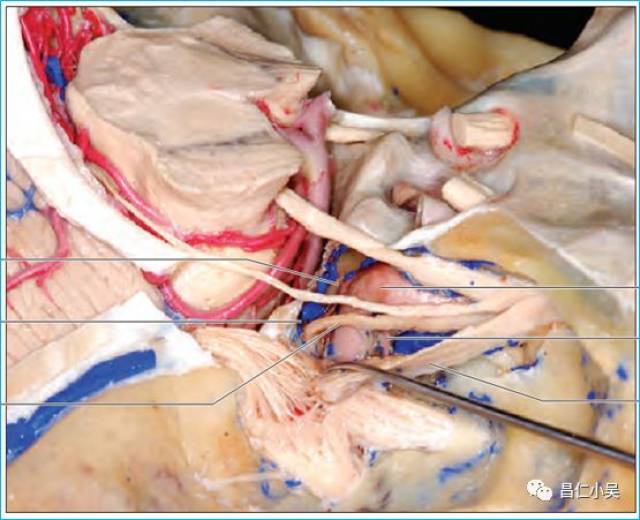

神经解剖外传——简单又不简单的滑车神经

神经解剖外传——简单又不简单的滑车神经

②切迹中间隙内主要有:pca,sca,滑车神经.

《系统解剖学》课件 Ⅳ,滑车神经 纤维成分:躯体运动纤维 行径:中